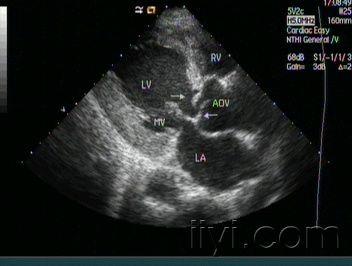

左冠状动脉主干动脉瘤超声示意图-刘海艳